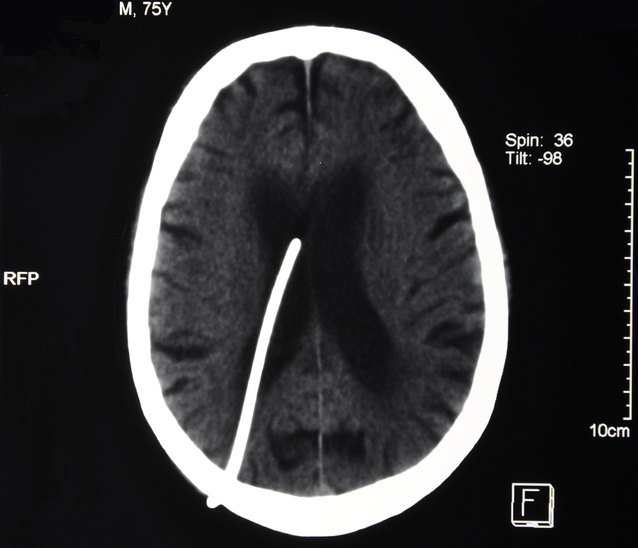

Babies born with hydrocephalus (congenital) and adults or children who develop it (acquired) usually need prompt treatment to reduce the pressure on their brain. This is usually done with a shunt.

During surgery, a thin tube called a shunt is implanted in the brain. The excess cerebrospinal fluid (CSF) in the brain flows through the shunt to drain into the abdominal cavity where is absorbed. Approximately 1300 new shunts (UK shunt registry) are inserted in the UK each year.